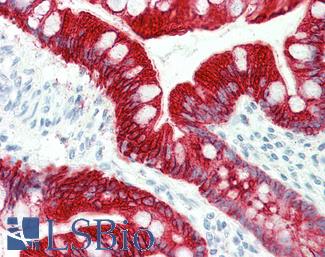

Anti-KRT20 / Cytokeratin 20 antibody IHC of human small intestine. Immunohistochemistry of formalin-fixed, paraffin-embedded tissue after heat-induced antigen retrieval. Antibody LS-B5959 dilution 1:50. This image was taken for the unconjugated form of this product. Other forms have not been tested.

CK20 (KRT20)